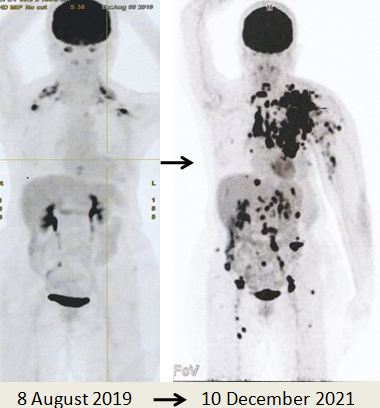

Due to the massive metastasis as shown in the PET scan done on 10 December 2021, Lucy had no choice but to proceed with chemotherapy. Indeed the cancer had spread extensively.

8. PET scan on 14 April 2022 showed good response indeed.

1. Amazing results of chemotherapy. Compare these three pictures –

Left: After surgery Lucy was on alternative therapy, refusing to undergo chemotherapy. The result was extensive metatastasis (middle). Right: Lucy has no choice but to go for chemotherapy. The outcome of 6 cycles of chemotherapy was just fantastic! In my 25 + years dealing with cancer patients, I have never seen such a great outcome of chemotherapy. Salute the oncologist! You rescued her!

In fact, the results were so unbelievable that one is tempted to ask if it is for real and not a fake? My answer is NO, detailed study of the PET scan results below are real! Study the images carefully – those before and after  chemotherapy.

As demonstrated by the outcome of this case, Lucy had taken the wrong path. Twenty months after doing what she thought was the right things to do, Lucy’s cancer spread like wild fire. There were metastases to regional and distinct lymph nodes, subcutaneous nodules, lung, peritoneum and bones (see the pictures above).

I may say I could not believe what I saw in the PET scan – it was a terrible disaster indeed. Lucy had committed  a tragic mistake.